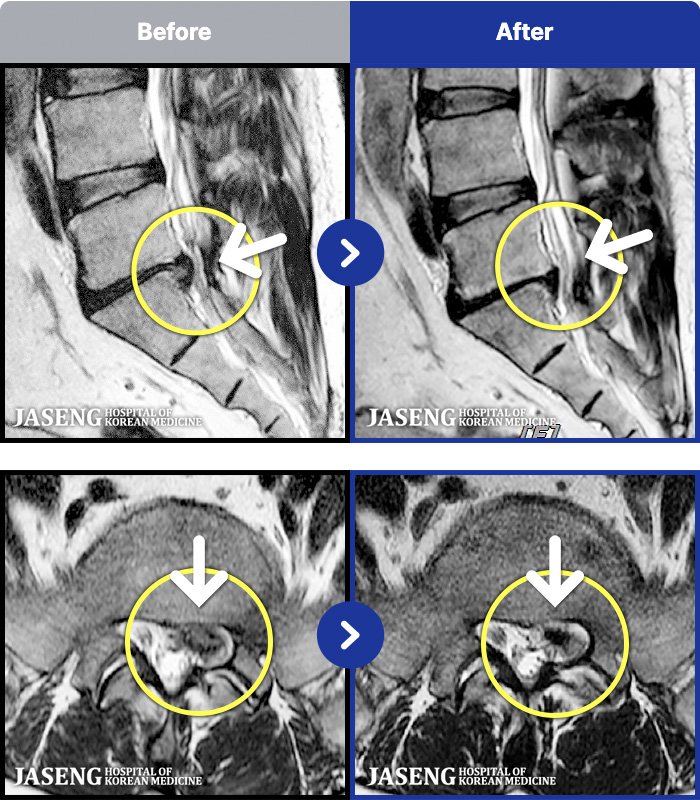

MRI ġ

1,304 MRI ũ ʸ Ȯϼ.